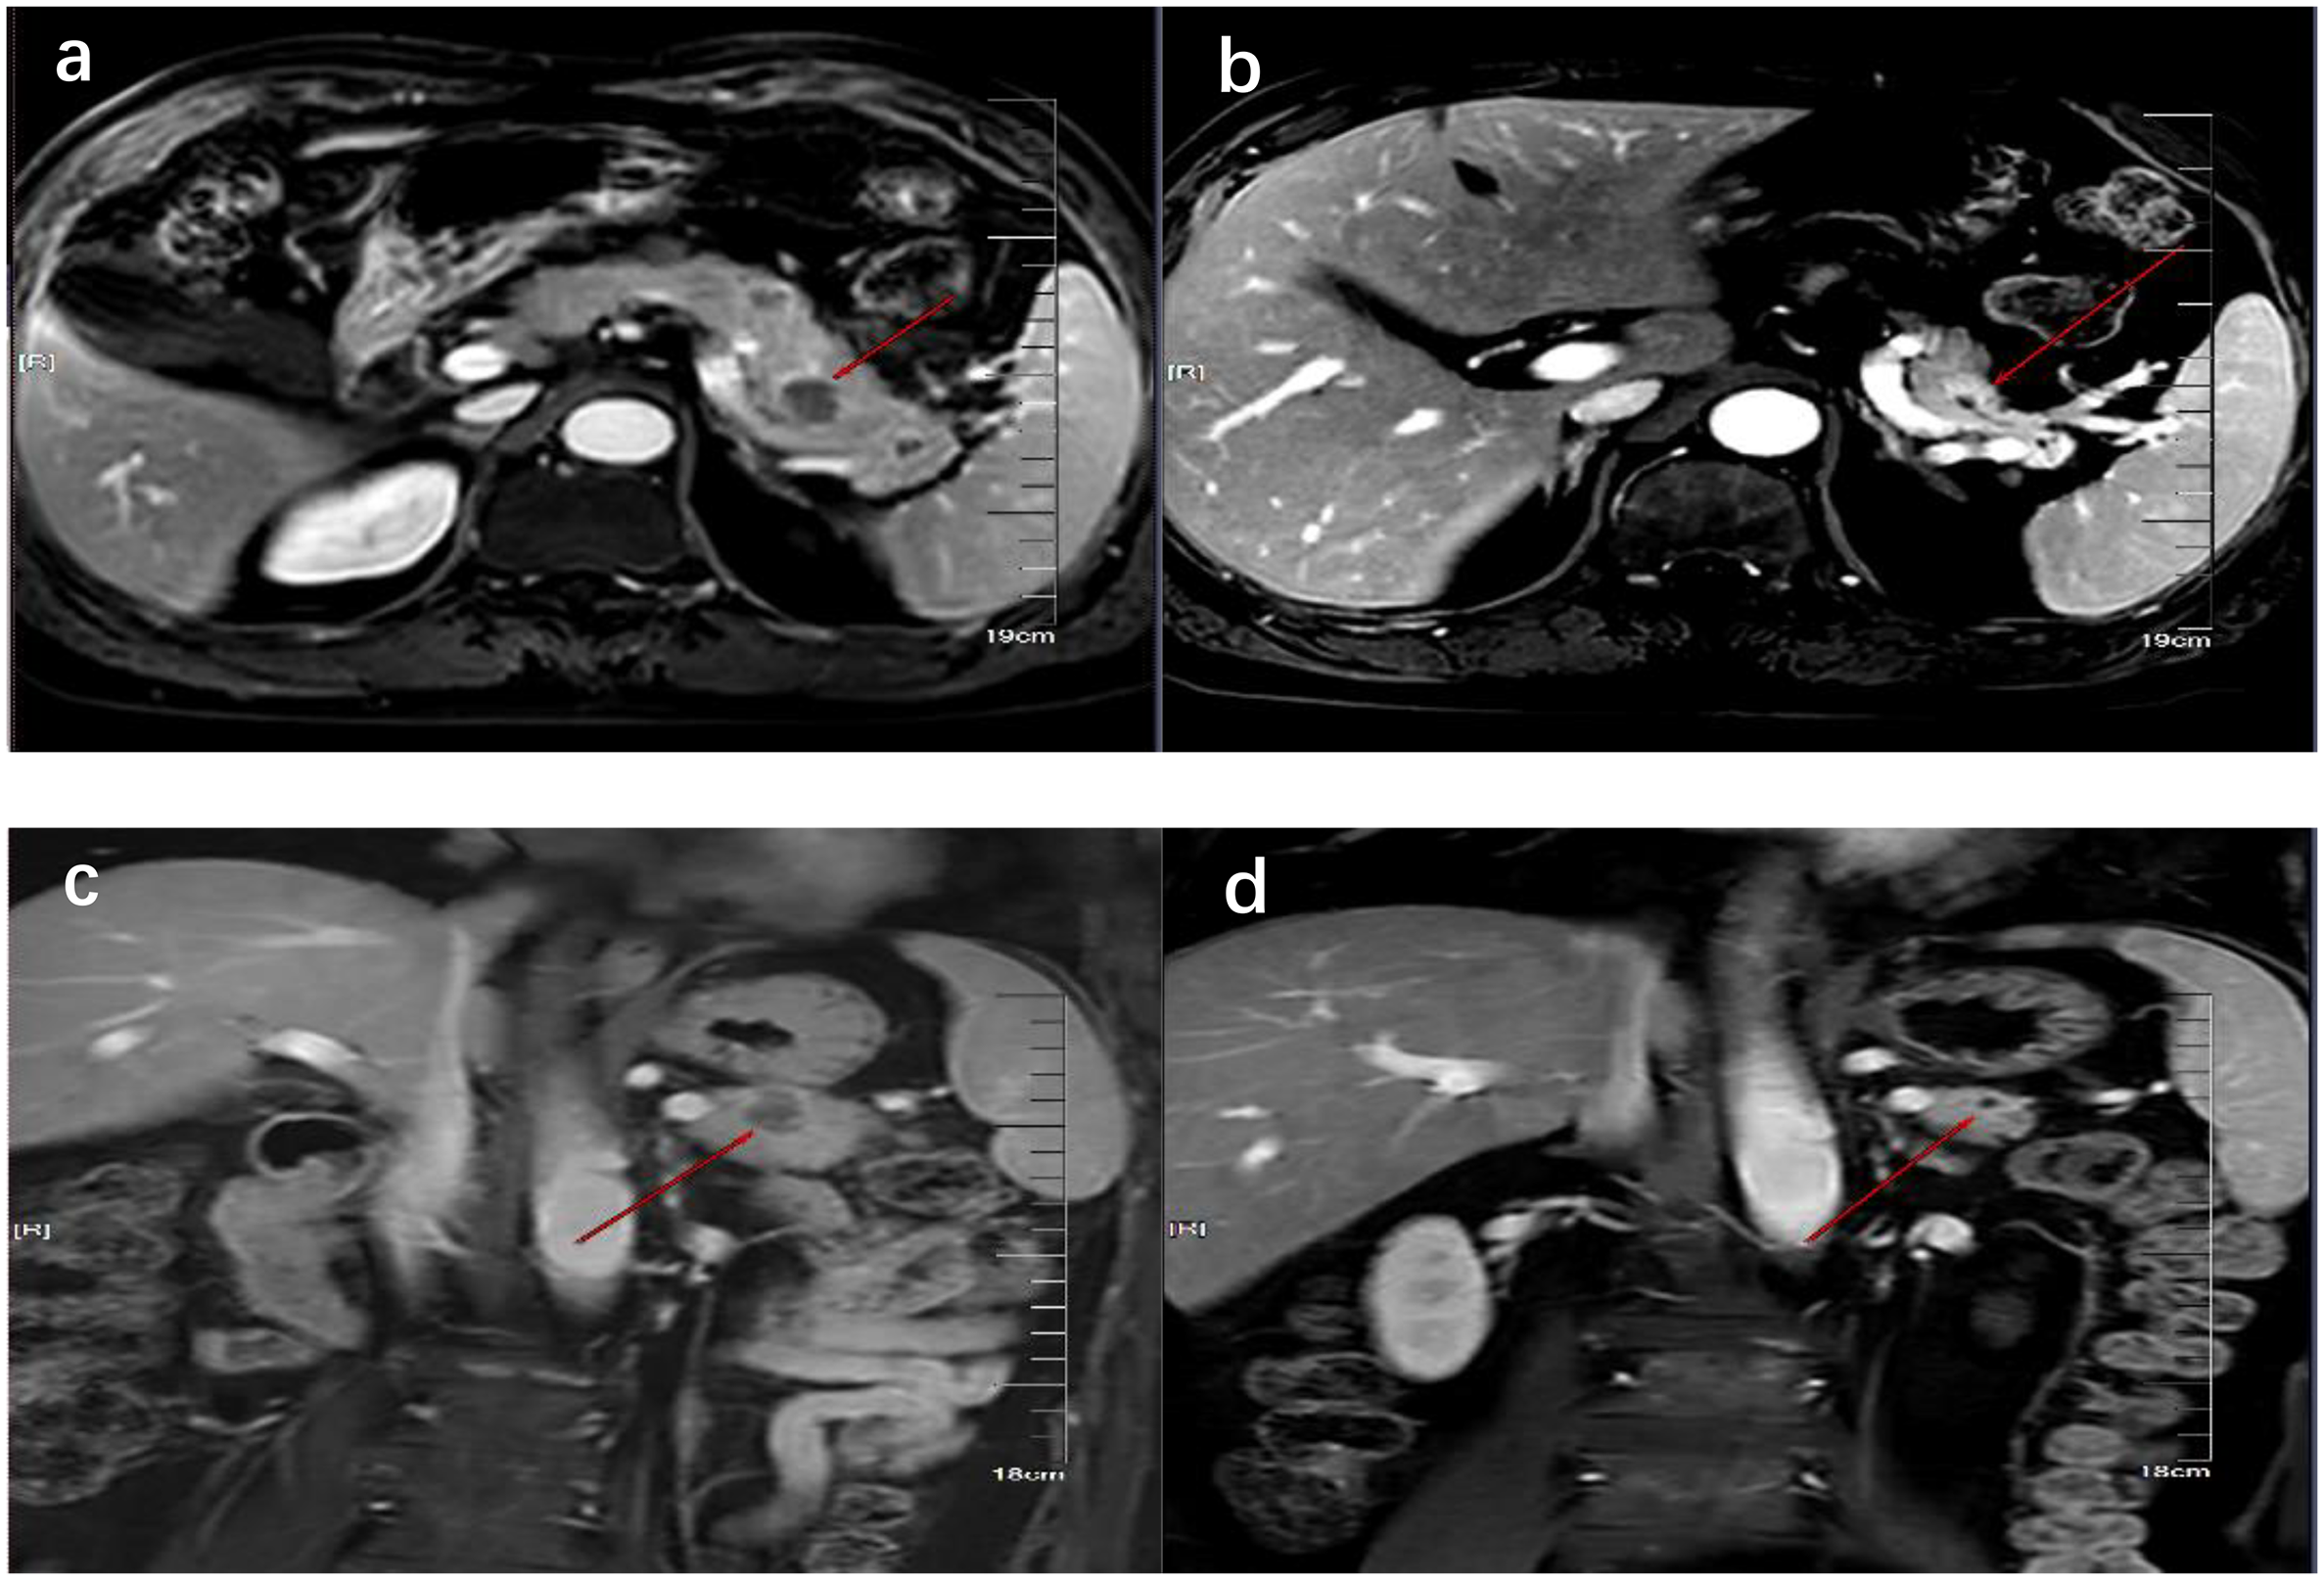

Figure 3

MRI showed the comparison of pancreatic lesions before (A, C) and after (B, D) the treatment of chemotherapy. (A, B) are MRI images of horizontal pancreas before and after treatment, and (C, D) are MRI images of coronal pancreas before and after treatment. The red line arrows point to the location of pancreatic lesions before and after treatment.

On 6 October 2023, he underwent 18F-FDG PET/CT for bone pain, which demonstrated that the dense streak shadow with low glucose metabolism in the upper lobe of the left lung was consistent with change after treatment and tumor activity was inhibited. Moreover, the presentation of PET was also consistent with postoperative manifestation of prostate cancer, and no abnormal hypermetabolic lesions were found in the surgical area. Hypermetabolic activity and osteolytic bone destruction sized about 3.8 cm × 3.2 cm were distinguished in left acetabulum lesion, which was considered bone metastasis (SUV max = 7.3). In addition, there were lesions with hypermetabolic activity in the pancreas, which was also supposed to be metastases (SUV max = 4.2) (Figures 2A, D), and the largest one sized about 5.1 cm × 2.8 cm on MRI (Figures 3A, C). The conclusion of 18F-PSMA-1007 PET/CT was in accordance with 18F-FDG PET/CT (Figures 2B, E). Then, 18F-NOTA-JR11 PET/CT was performed to compare with 18F-PSMA-1007 PET/CT and 18F-FDG PET/CT, which showed multiple hypermetabolic lesions in the head and tail of the pancreas, exhibiting an abnormally high 18F-NOTA-JR11 uptake (SUV max = 17.6) (Figures 2C, F) but a moderate 18F-FDG and 18F-PSMA-1007 uptake. Therefore, the high possibility of G2 grade primary neuroendocrine tumors (NETs) of the pancreas was considered. Moreover, the lesion in the left acetabulum presented the similar pattern of uptake (SUV max = 31.9), which was considered pancreatic NET with bone metastasis. The serum levels of tumor markers were as follows: Carbohydrate antigen 199 (CA199) of 33.68 U/mL and Neu-ron specific enolase (NSE) of 23.74 ng/mL. To identify the primary lesion, we performed endoscopic ultrasound-guided fine-needle aspiration biopsy and percutaneous puncture under ultrasound guidance for bone biopsy. The result of bone puncture biopsy supported small-cell carcinoma, which was likely to originate from the lung based on the immunohistochemistry and morphology analysis, and immunohistochemistry results were a positive staining for Ki-67 (approximately 80%), CKpan, TTF-1, CgA, Syn, Insulinoma-associated protein 1 (INSM1), Retinoblastoma gene product (RBGP), and P53 (approximately 80%) and a strongly positive staining for SSTR2; simultaneously, it indicated a negative staining for NapsinA, P504S, PSA, Vimentin, CK7, P40, and NKX3.1 (Figure 4C). For the tissue of pancreas, abnormal cells were found in the coagulation tissue, which supported the diagnosis of small-cell neuroendocrine carcinoma (NEC), and immunohistochemistry analysis showed a positive staining for Ki-67 (approximately 40%), P53, CK, Syn, CD56, CK19, INSM1, and alpha-thalassemia mental retardation X-linked (ATRX) and a negative staining for CK7, CK20, villin, CEA, CgA, and RbGP (Figures 4A, B). In the meanwhile, pancreas tissue sample was obtained, and a comprehensive genomic profiling was performed by high-throughput sequencing using a 520 cancer-related gene panel, which demonstrated RB1 p.Y454 and TP53 p.G266R variant (germline mutation). The treatment consisted of cisplatin + etoposide + Atezolizumab + denosumab starting on 15 November, and, after 2 courses of treatment, the overall efficacy was evaluated as partial response, and the largest pancreas lesion size was about 3.4 cm × 1.5 cm (Figures 3B, D).